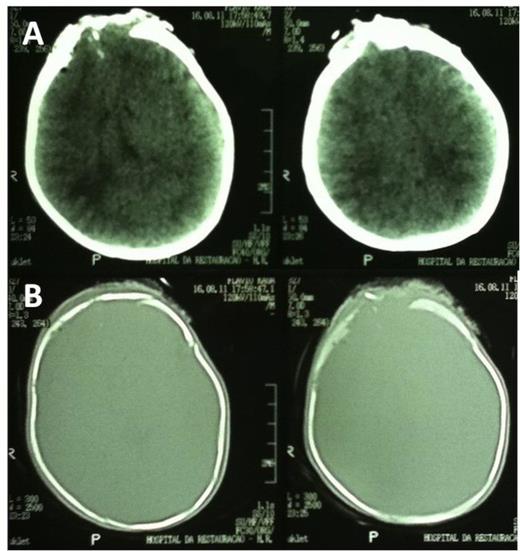

The patient was transferred to the intensive care unit and a CT scan of the brain was performed 48 hours after surgery (Fig. 4).